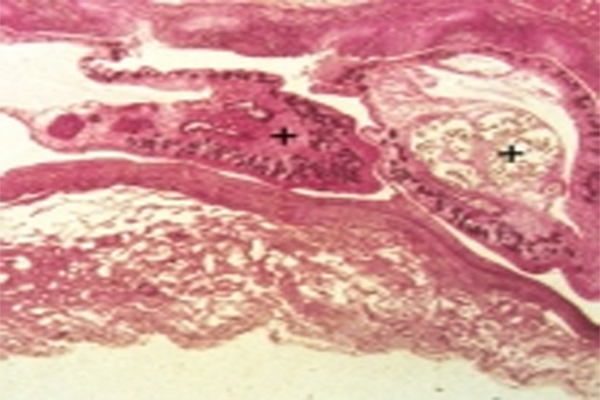

猪姜片吸虫病与华支睾吸虫病 华支睾吸虫的致病虫期

猪病防治:姜片吸虫病 姜片吸虫呈肉红色,肥厚宽大,像切下的姜片,因而得名。成虫寄生在猪的小肠内,异体受精或自体受精。一个成虫每天产卵1.5~2.5万个。卵随粪便排出,落入水中,侵入中间宿主扁卷螺体内,发育成熟为尾蚴。逸出后,附在水葫芦、水浮莲、茭白、浮萍等上面。脱